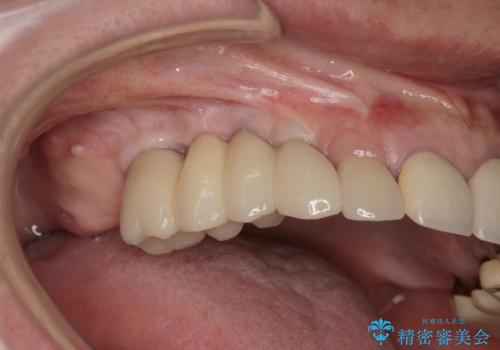

他院で中途半端に終わってしまったインプラント治療

- 他院で1本インプラントを入れたまま治療に通うことができなくなり、途中からの治療を希望され来院されました。

既に埋入されているインプラントは位置が悪いのでそのまま骨内に留置することとし、新たに咬合機能を回復すべく3本のインプラントを埋入すると同時に吸収した骨幅を増やし、安定してインプラントで噛める環境整備を目指します。

インプラントが長持ちするために、インプラント周囲の十分な骨量・角化歯肉の存在・安定した咬合を一つづつ整備する治療を行いました。